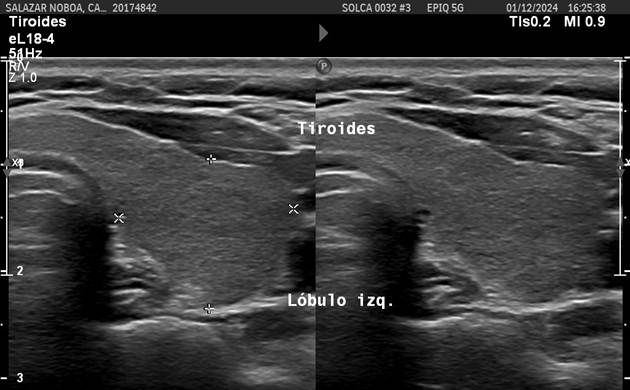

A PET-CT scan in December 2023 revealed persistent hypermetabolic lymphadenopathy in the left lateral cervical region (SUVmax 2.4), as well as increased metabolism in the right thyroid lobe. A cervical ultrasound in December 2024 identified a 0.69 x 0.72 cm hypoechoic solid thyroid nodule, classified as TIRADS 4A (Figure 3). The fine-needle aspiration biopsy (FNAB) was reported as Bethesda IV, and management was decided upon with close monitoring.

Figure 3

Cervical ultrasound: Thyroid nodule classified as TIRADS 4A.

Source: SOLCA Intranet - Guayaquil.